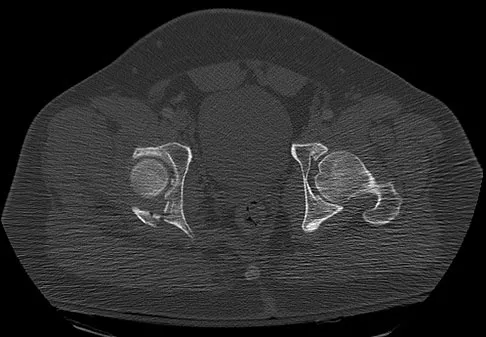

Which of the following choices best describes the fracture pattern shown in Figures 2a through 2c?

The fracture pattern shown in the radiographs is a fracture of the posterior column. The only line interrupted on the AP pelvis is the ilioischial line. The obturator oblique view shows that the iliopectineal line is intact as is the outline of the posterior wall. The iliac oblique view shows an interruption of the ilioischial line and an intact anterior wall. Therefore, this fracture is a fracture of the posterior column. Letournel E, Judet R: Fractures of the Acetabulum, ed 2. Berlin, Germany, Springer Verlag, 1993.

- Matta J: Surgical treatment of acetabular fractures, in Browner BD, Jupiter JB, Levine AM, et al (eds): Skeletal Trauma, ed 3. Philadelphia, PA, WB Saunders, 2003, vol 1, pp 1009-1149.